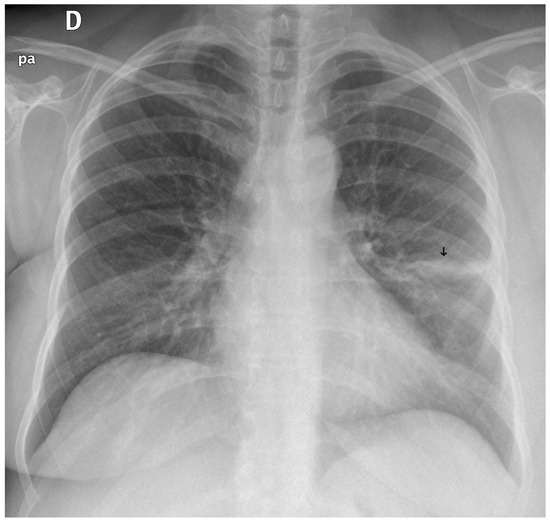

Figure 10. A false negative example of an alveolar opacity (black arrow).